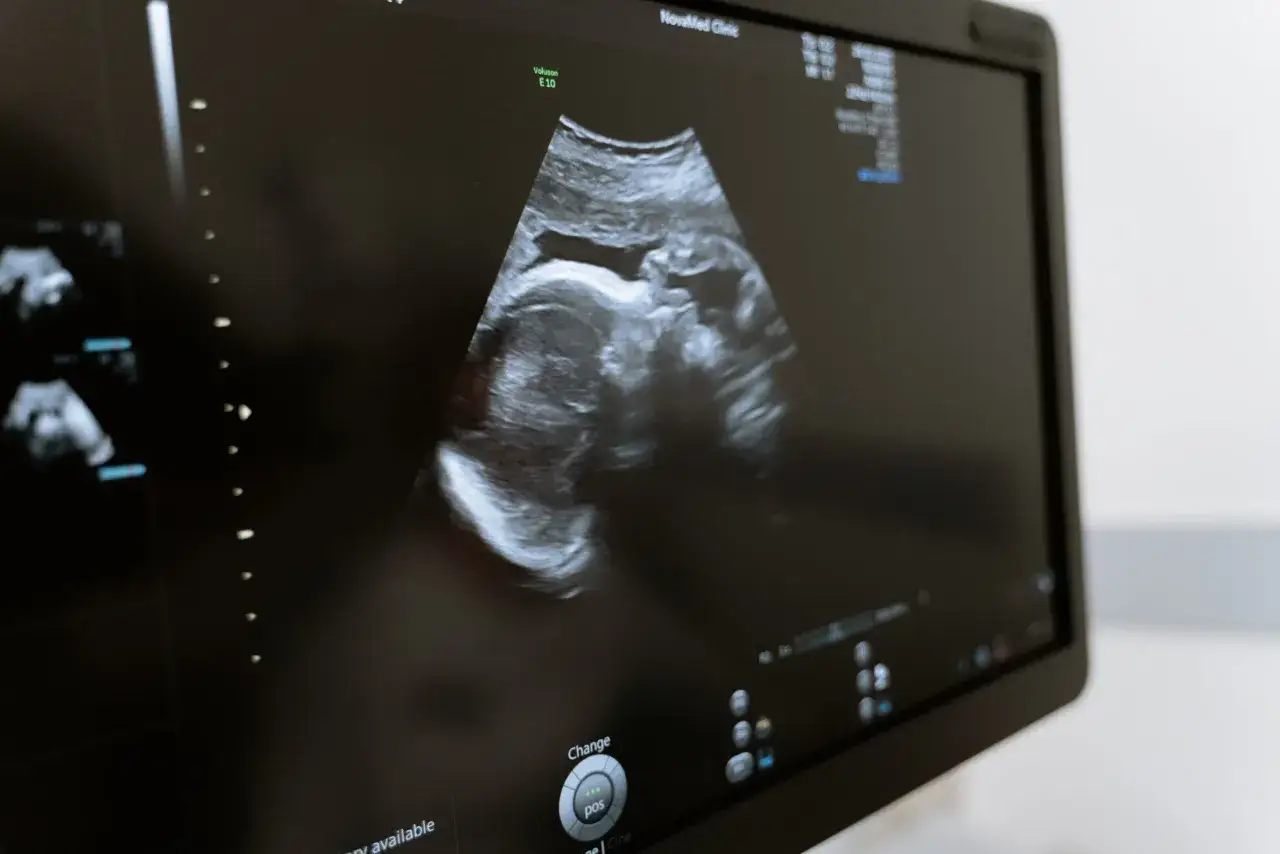

USG genetyczne: Co oznaczają tajemnicze skróty NT, NB, DV?

Badanie USG genetyczne, zwane również USG I trymestru, jest niezwykle precyzyjnym badaniem ultrasonograficznym, wykonywanym między 11+0 a 13+6 tygodniem ciąży. Podczas tej wizyty doświadczony lekarz ocenia nie tylko ogólną anatomię płodu, ale przede wszystkim tzw. markery wad genetycznych. Wśród nich najważniejsze są:

- NT (przezierność karkowa): Jest to grubość fałdu skóry na karku płodu, mierzona w milimetrach. Zwiększona przezierność karkowa jest jednym z najistotniejszych markerów wskazujących na podwyższone ryzyko wad genetycznych, w tym zespołu Downa.

- NB (kość nosowa): Lekarz ocenia obecność lub brak kości nosowej. Jej brak lub niedorozwój może być związany z niektórymi zespołami genetycznymi.

- DV (przewód żylny): Badanie przepływu krwi w przewodzie żylnym, czyli naczyniu łączącym pępowinę z sercem płodu. Nieprawidłowy przepływ może wskazywać na problemy kardiologiczne lub genetyczne.

- TV (zastawka trójdzielna): Ocena przepływu krwi przez zastawkę trójdzielną w sercu płodu. Nieprawidłowości w tym obszarze również mogą być markerem wad.

Te markery są niezwykle ważne, ponieważ ich prawidłowe wymiary i przepływy znacznie obniżają ryzyko wystąpienia wad genetycznych.